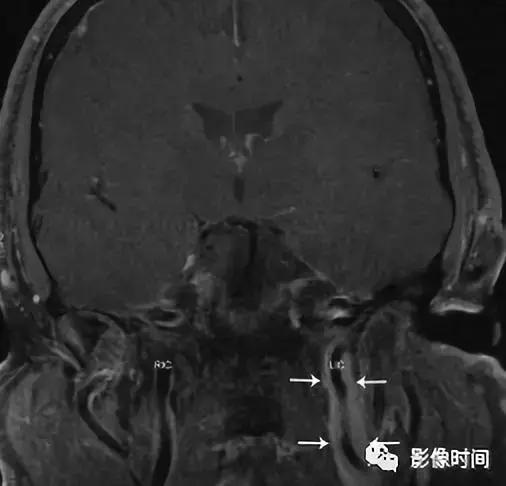

轴位 T1WI+C 显示不均匀强化肿块,完全包裹左侧颈内 (LIC) 和颈外动脉 (LEC)。注意左侧颈内动脉的管腔与右侧颈内动脉 (RIC) 的管径一致。